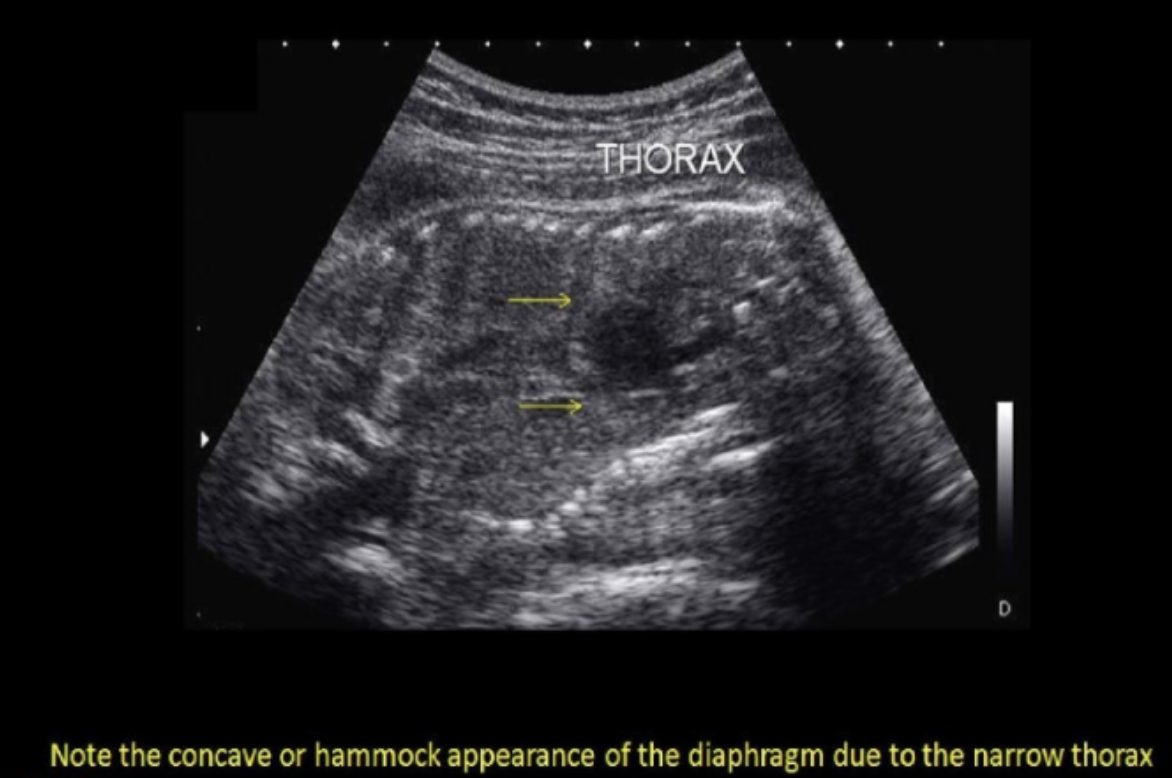

if the radiologist suspects potter syndrome + requests that you perform a thoracic circumference. how will this measurement assist in the dx? Potter syndrome usually shows

.

a) cardiomegaly + diaphragmatic hernia, which will increase the size of thoracic cavity

b) pulmonary hyperplasia, which leads to enlarged thorax

c) a narrow thorax due to acardia

d) a bell-shaped thorax that is much more narrow than the abd cavity